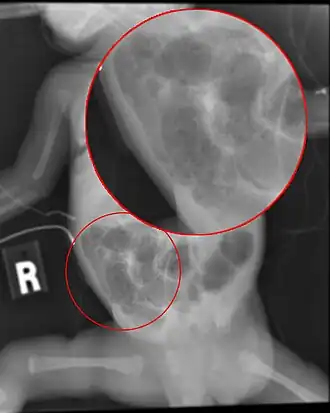

![]() Radiografía de abdomen de un bebé con enterocolitis necrotizante. | ||

El diagnóstico se hace clínicamente, pero se puede usar apoyo de imágenes, como una radiografía abdominal. Algunos signos en la radiografía de abdomen que apoyan el diagnóstico con la dilatación de asas intestinales, edema de la pared intestinal, y el signo más característico que define esta enfermedad, es la llamada neumatosis intestinal,[1][2] que es la presencia de aire adentro de la pared intestinal. Se utiliza para clasificar, las llamadas etapas de Bell:[2][3]